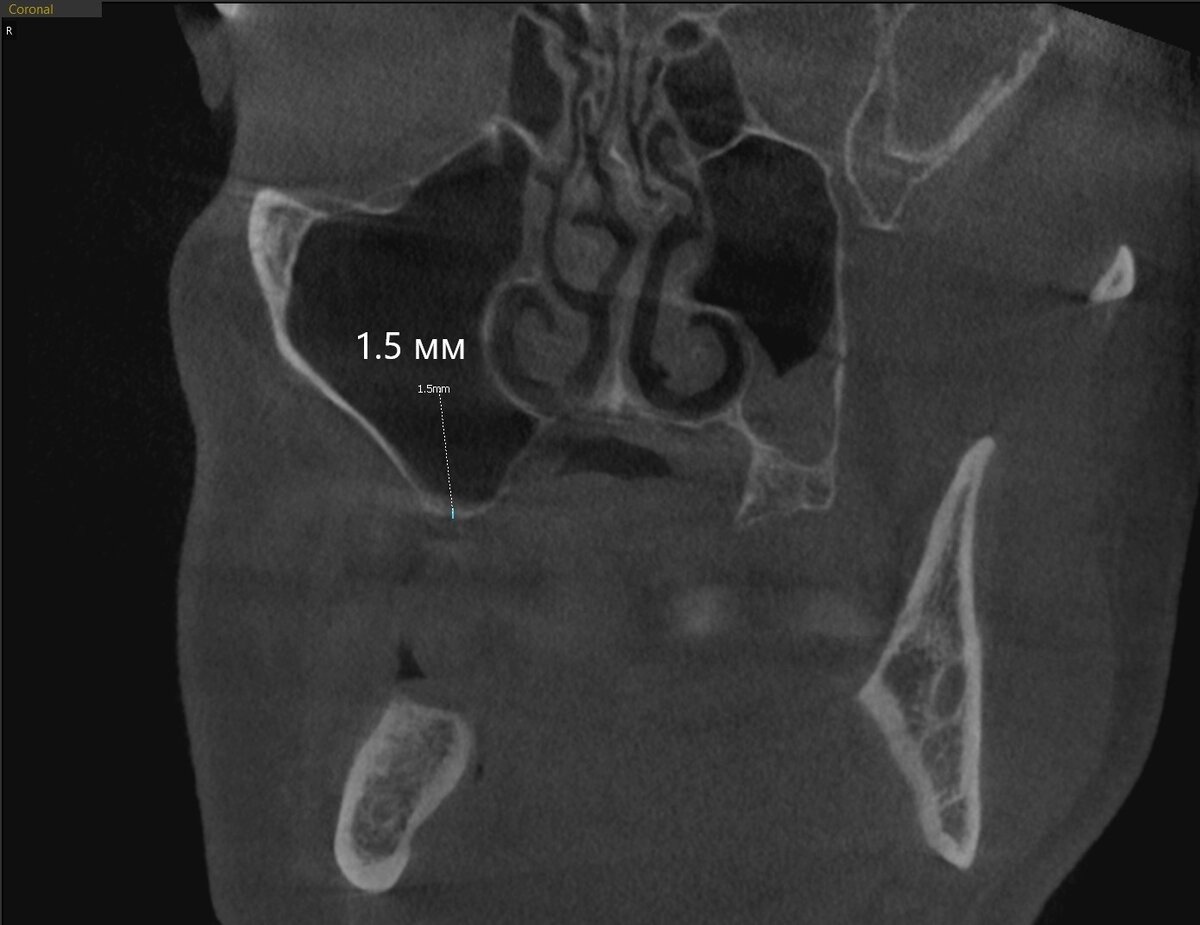

А чем же? Находим причинный зуб:

Есть большая вероятность, что содержимое - гнойное.

Мы сами дистанционно связались с доверенным ЛОР-врачом и поинтересовались, опасно ли проводить синус-лифтинг справа, когда такая засада слева. ЛОР оценил протоки и дал добро.

Зуб с противоположной стороны (2.6) был удалён, сообщение с пазухой минимальное и имплантолог не стал расширять доступ. Проверил дно костной лунки и отправил пациента на КЛКТ. Вот результат:

А "киста" сдулась. И сделала она это ещё ДО удаления зуба, 100%. Подозрение на ретенционную "кисту", такую же, как была описана мною вот в этом случае:

Гноя не выявлено, в общем. Это очень хорошо.